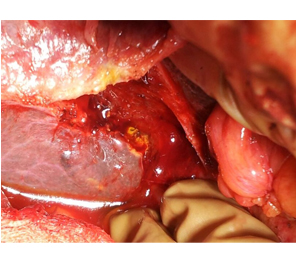

Post operative PTBD gram showing a patent high hepaticojejunostomy